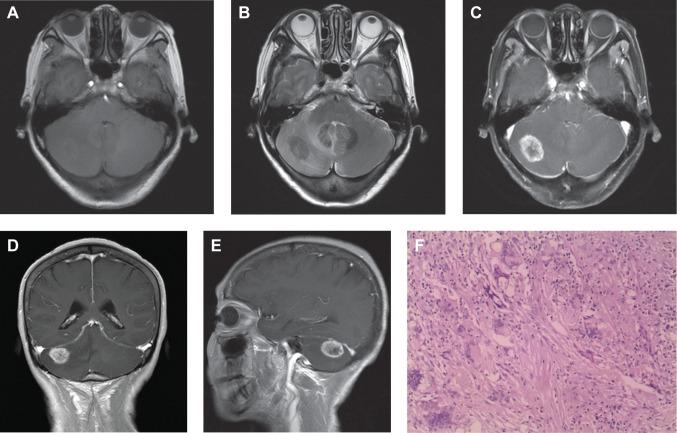

Central nervous system (CNS) cryptococcosis is an opportunistic fungal infection that typically occurs in patients with reduced immunological function, such as patients with AIDS, patients receiving organ transplants, or patients receiving corticosteroid and immunosuppressive therapy. CNS cryptococcosis rarely occurs in immunocompetent patients. CNS cryptococcosis is characterized by meningitis and encephalitis and occasionally forms isolated granulomas. Isolated cerebellar cryptococcoma is a rare condition, especially in immunocompetent patients, and the misdiagnosis rate is high. A definite diagnosis must be based on pathology. To raise awareness of this disease, the clinical data of a patient with cryptococcomas in the right side of the cerebellum are reported.

中枢神经系统(CNS)隐球菌病是一种机会性真菌感染,通常发生在免疫功能低下的患者中,如艾滋病患者、接受器官移植的患者或接受皮质类固醇和免疫抑制治疗的患者。CNS 隐球菌病很少发生在免疫功能正常的患者中。CNS 隐球菌病的特征是脑膜炎和脑炎,偶尔形成孤立性肉芽肿。孤立性小脑隐球菌瘤是一种罕见的情况,尤其是在免疫功能正常的患者中,误诊率很高。明确的诊断必须基于病理学。为了提高对这种疾病的认识,报告了一例右侧小脑隐球菌瘤患者的临床资料。